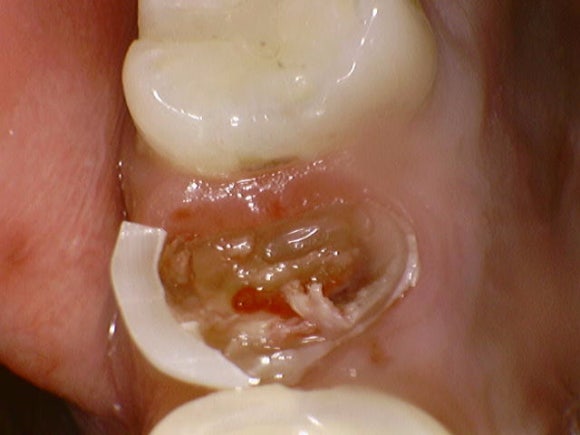

충치를 제거하는 중입니다.

아직 다 제거한 것도 아닌데

한 쪽면을 제외하고 성한 곳이 하나도 없습니다.

그래도 괜찮습니다.

뿌리의 길이가 충분히 길기 때문에,

잇몸을 약간 벗겨내어

뿌리로부터 머리를 빌려옵니다.